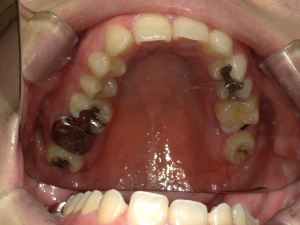

30代 女性 奥歯 インプラントGBR

| 年代・性別 | 30代・女性 |

| 治療回数 | 1回 ※術前治療・検査除く |

| 治療期間 | 5ヶ月 |

| 料金 | ¥60,000(税込) |

GBR(Guided Bone Regeneration:骨再生誘導法)とは、インプラント治療において、骨の厚みや高さが足りない場合に行う歯槽骨を再生する方法です。骨量不足の患者様でも、骨造成を行うことでインプラントの埋入に必要な骨の高さや厚みが得られます。 GBR(再生誘導法)は、骨が痩せて十分な骨量が確保できない患者様に、骨の再生によってインプラントの埋入を可能にする治療方法の一つです そのような骨が欠損した部分では、骨を作る「骨芽細胞」よりも、骨にならない「線維芽細胞」の方が増殖しやすいという特徴があります。そのためGBRでは、骨形成の妨げになる繊維芽細胞の侵入を防ぐため、骨を増やしたい部分を「メンブレン」という人工膜で覆い、その中に自家骨や人工の骨補填材を詰めて骨芽細胞の増殖を促します。 |

| 副作用 | 術後に腫れ・痛みが出る可能性がある。 |